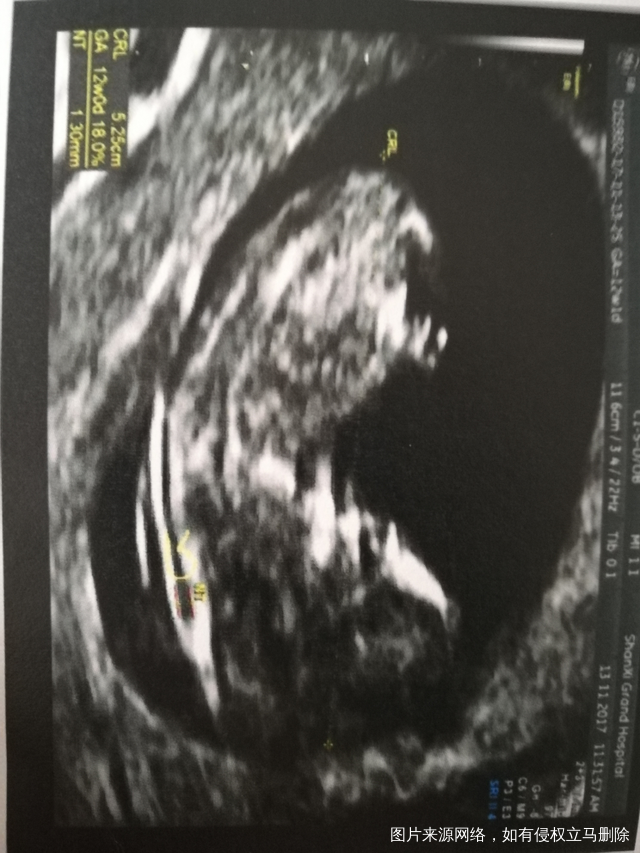

谁会看男孩女孩,来帮我看看